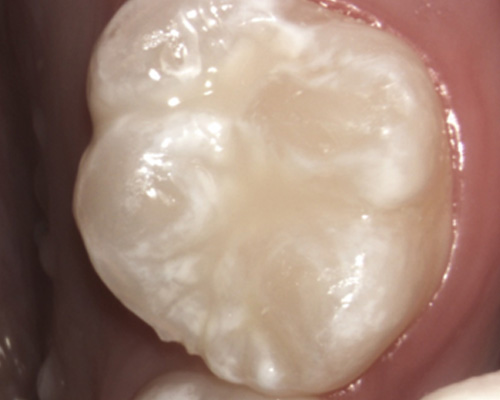

Having a fissure sealant is good to protect the tooth from a decay.

Before

Having a fissure sealant is good to protect the tooth from a decay.

Before